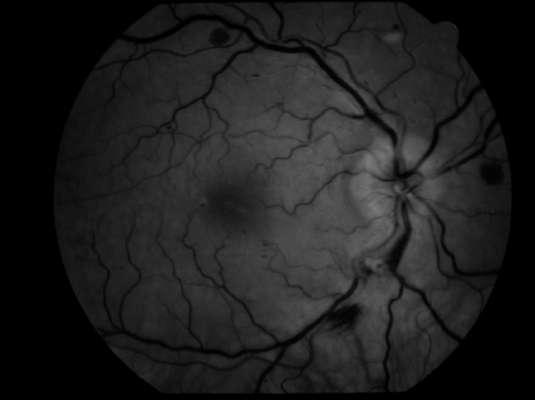

Imágenes aportadas por Dr. Cristian Sánchez

ü La degeneración macular relacionada a la edad es la causa más frecuente de pérdida de visión irreversible en personas mayores de 60 años

ü La patogenia es multifactorial, en que además del envejecimiento (principal factor de riesgo) los factores de riesgo genéticos y ambientales (Tabaquismo, obesidad abdominal) juegan un rol determinante

ü Su primera manifestación son las drusas sin embargo el proceso puede evolucionar a la forma seca o húmeda

ü La forma húmeda se caracteriza por la presencia de membrana neovascular coroidea que crece bajo el epitelio pigmentario y luego bajo la retina. Estos vasos de neoformación se originan en la coriocapilar, proliferan y penetran al espacio subepitelial a través de una ruptura de la membrana de Bruch

ü El desprendimiento de epitelio pigmentario puede preceder la neovascularización coroidea, y en ese caso su contenido es seroso, cuando se asocia a neovascularización coroidea su contenido es fibrovascular

ü Al examen oftalmoscópico, en caso de tener una membrana neovascular, se detecta un solevantamiento retinal, habitualmente redondeado y generalmente rodeado de un halo de sangre subretinal. El solevantamiento se debe a la presencia de líquido o edema retinal. La membrana neovascular puede ser extrafoveal, alejada del centro, pero en la mayoría de los casos es subfoveal

ü Una complicación inusual es la hemorragia subretinal masiva, lo que en algunos pacientes se asocia a terapia anticoagulante

ü Angiografía con fluoresceína en la membrana MNVC Tipo Ia (DEP fibrovascular): se caracteriza por presentar área hiperfluorescente irregular visible desde un tiempo arteriovenoso precoz que incrementa la fluoresceina en tiempos tardíos con poca o nula difusión

2.G. MEMBRANA NEOVASCULAR COROIDEA (MNVC)

Clement F . “Angiografía”. Diagnóstico por la imagen en la retina, Sociedad Española de Retina y Vítreo, editado por Ignasi Jügens, Elservier, 2014, pp 41-66 Juan Verdaguer, T. (2010). Degeneración macular relacionada a la edad. Revista Médica Clínica Las Condes, 21(6), 949–955. doi:10.1016/s0716-8640(10)70620-9

A B